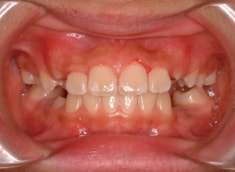

治療前

治療後(12ヶ月後)